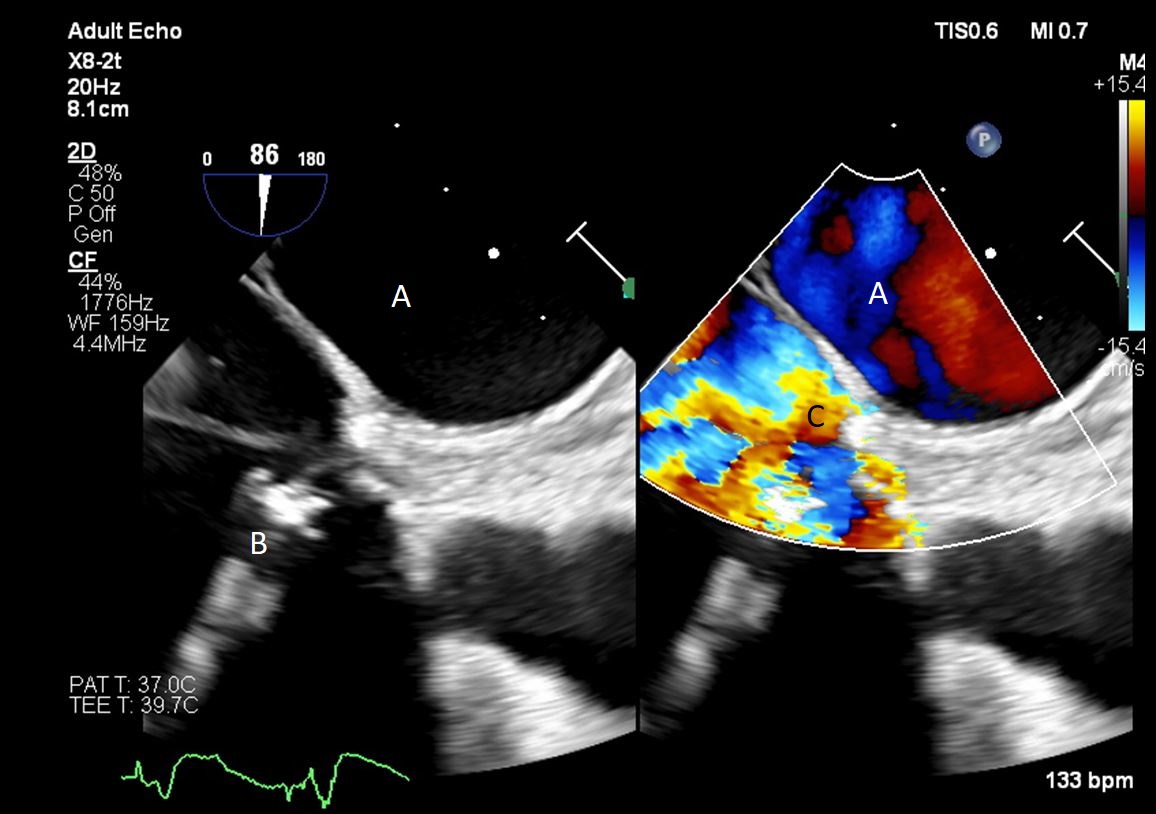

Impella (A) in the LV cavity caused disruption and damage to subvalvular apparatus resulting in flail segment (B) of the mitral valve.

Fig. 4.Impella (A) placement causing disruption and damage to subvalvular apparatus resulting in mitral valve flail (B) and mitral regurgitation (C).